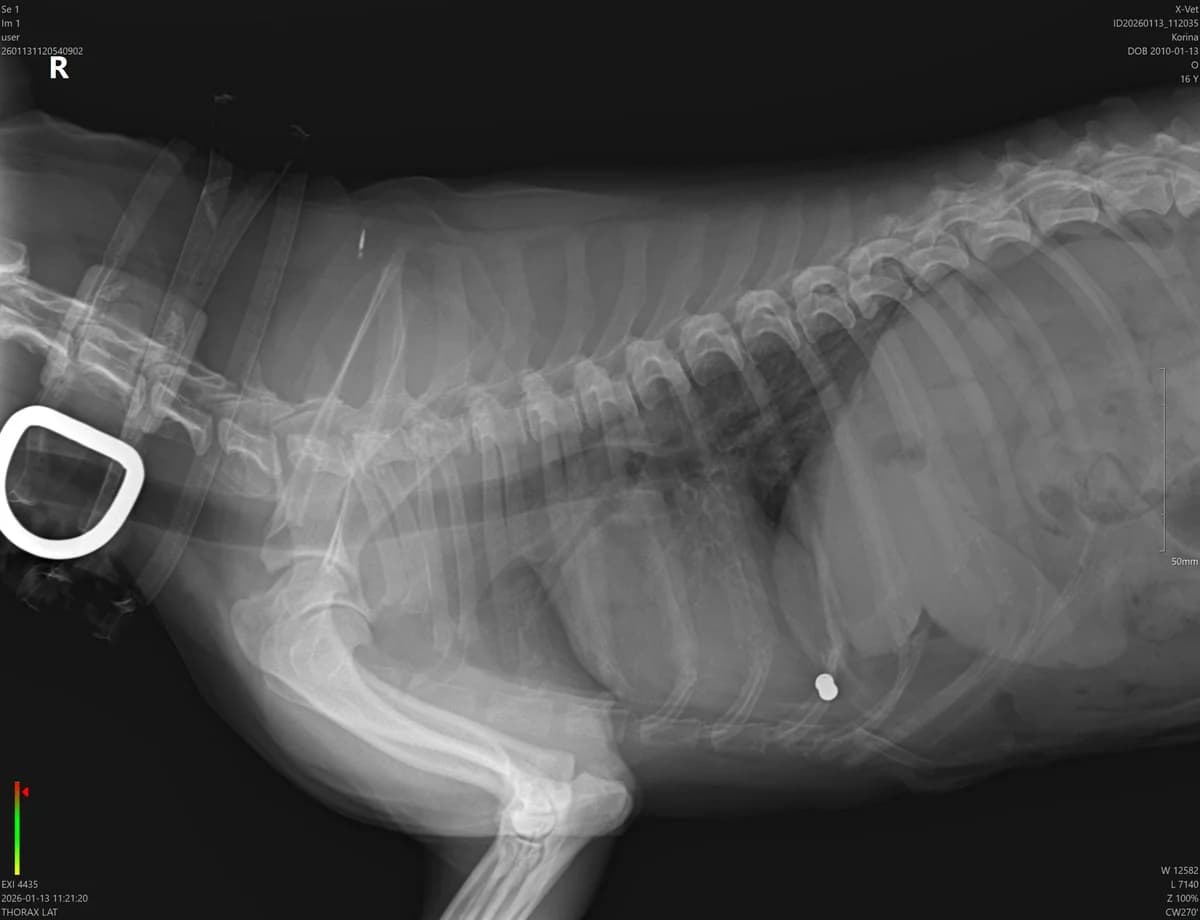

26.03.2026 THE CORINE HAS AFTER 2 MONTHS FROM THE OPERATION OF THE SONO WITHOUT VIEW, THE ROAD IS CLEAN, CLEAN DUTCH WITHOUT TECUTIN, IT IS POSSIBLE THAT THE FEATURES IN BRUSSIA WERE EARLY EARLY UNCHARGE. The next check scheduled for 4 months, if her condition doesn't get worse, we're asking very much for a LAST HOME FOR THIS MIGHTY PHONE, Korinka, 8 kg of love, joy and pure energy. Although he is 11 years old, he is a cheerful and playful dog that he enjoys every day to the fullest. Such a little black sunshine ♦ that gives away a smile and a good mood wherever it comes 🙂 Currently lives in temporary care in the apartment in Bratislava with two other fenkaki and it is a problem-free, grateful and tender pheno. It is already completely treated, vaccinated, castrated. We're looking for a home where he'll be a family member and he won't be discouraged by the risk that the cancer will come back to us, if you want to indulge Korinke in a kind home in good or bad, please write to us at the 22.02.2026 After surgery, she recovered incredibly quickly, and for a few days, she was running around like nothing happened. The control sono has turned out excellently no visible changes. And she doesn't realize her diagnosis, she lives with the present, enjoys the caress, the soft blanket, from every step of the grass. It is currently in temporary care in Bratislava and it is a smooth, thankful and tender pheno. Looking for Homes to Live Someone who has given her the last few months full of love, warmth and security. Someone who, despite uncertain prognosis, will show her that she too can have her own home. 13.01.2026 Where to start, it's very hard to write this post, we still can't process it... Corina, 8kg little female dog, was about to castrate today, a merry dog came to the veterina, and she had to investigate everything in the ambulance. Even though she was 11 years old, in that week, she seemed like a cheerful and energetic dog who enjoyed life to the fullest, little black sun. However, on admission, the doctor felt 3 tumors on the milk bar " common problem in uncastrated female dog of old age. However, pre-operative tests went well, blood normal, lung clean, heart no problem. But when the uterus was removed, where there were benign tumors and cysts on the ovaries at first sight, the doctor found a number of tiny tumors in the abdominal cavity, depending on the extent and shape, the most aggressive type of cancer, and the prognosis is very bad, the prognosis is that spleen, liver or other important organs have not yet been affected, but in a month's time Korinke may have had to help breathing twice today, but in the end, she would have managed very much